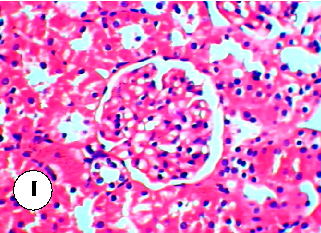

Figure 22

Figure 22 Chart

Supplementary biochemical or histological data from the plant oil-diazinon study, providing additional evidence for the protective mechanisms.

Protective effect of some plant oils on diazinon induced hepatorenal toxicity in …